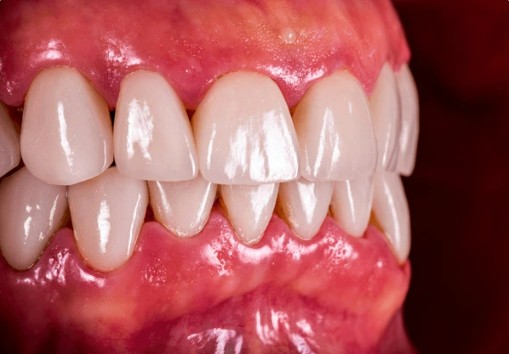

Dobrou zprávou ale je, že včasná dentální hygiena dokáže zánět dásní velmi často zcela zklidnit.

Jak se krvácení dásní řeší

Řešení vždy vychází z konkrétní situace, ale obvykle zahrnuje:

-

profesionální odstranění zubního kamene a plaku,

ošetření problematických míst,

individuální doporučení domácí péče,

kontrolu techniky čištění a mezizubních pomůcek.

Cílem není jen "aby dásně nekrvácely", ale aby byly dlouhodobě zdravé, pevné a bez zánětu.